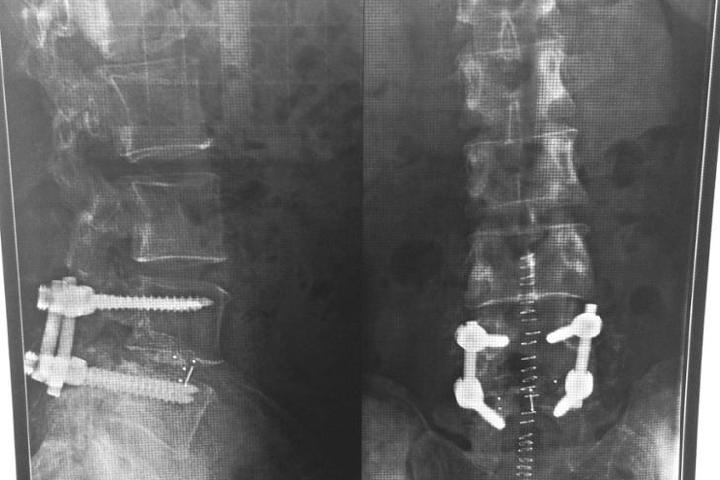

Nuestro proyecto es conseguir una vía de investigación que sepa por que los huesos no nos dejan de calcificar. Esta investigación es muy importante ya que nos puede ayudar a entender por que el cuerpo calcifica o descalcifica y por que lo hace. Hasta ahora se sabe poco o nada de por que nosotros con el paso del Tiempo seguimos calcificando. Nuestro problema surge cuando nos afecta a nervios y nos quita movilidad. Llegando en algunos caso a producir parálisis, sordera e insensibilidad.